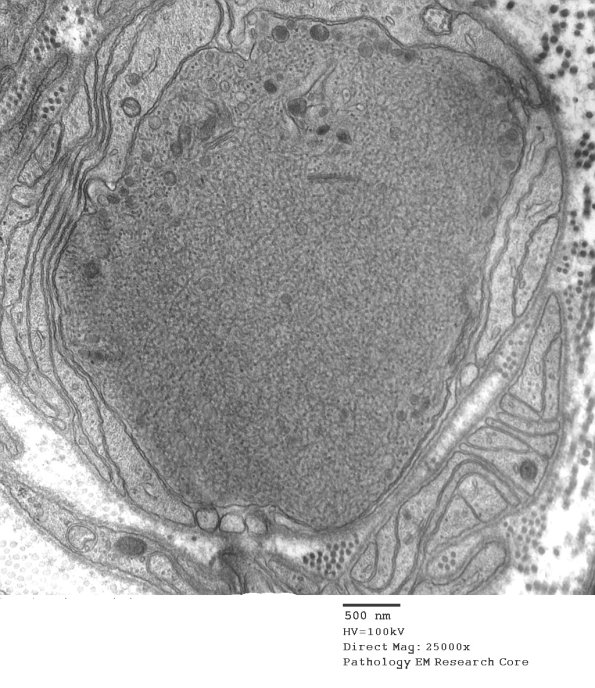

11H1,2 Shown is a band of Büngner with an axon swollen with tubulovesicular elements. (electron micrographs)